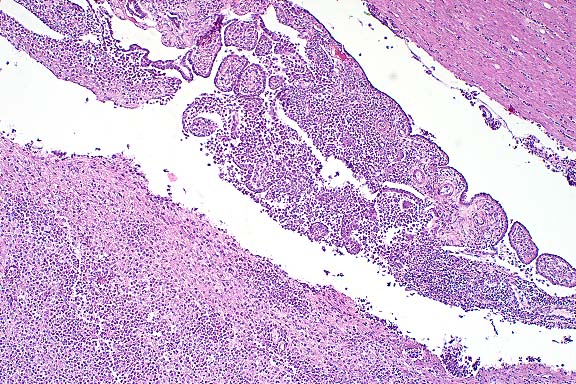

Case 1-1. Kidney. Note tubular ectasia and proteinaceous debris, interstitial lymphoplasmacytic infiltrate, profiles of rhabditiform nematodes, and multinucleate giant cell. 10x obj.

1. Kidney: Nephritis, granulomatous, multifocal and coalescing, moderate to severe, with interstitial fibrosis, tubular ectasia, and many larval and adult rhabditid nematodes, Miniature horse, equine, etiology consistent with Halicephalobus sp.